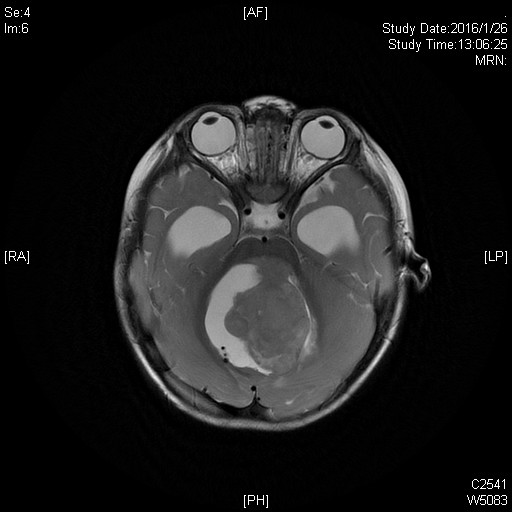

髓母细胞瘤是颅内恶性程度最高的胶质瘤,生长迅速,手术不易全部切除。经过神经外科科内讨论,为小萌制定了详细的手术方案,行肿瘤切除术。麻醉科也给予小萌特别的关爱,在手术室,麻醉科张欢主任和主治医师魏昌伟上下同时开工,一位动脉穿刺,一位股静脉植管。麻醉过程紧张有序,有条不紊。主刀医生王贵怀主任擅长高位颈髓和脑干肿瘤手术,处理四脑室肿瘤游刃有余。手术中肿瘤暴露、分离、切除、止血,步步为营,干净利落。手术很成功,肿瘤全切,约5.0mm×3.5mm,足有鸡蛋大小。术后小萌入ICU,在ICU的精心治疗下,他恢复很快,术后第2天返回普通病房治疗。术后住院日,小萌病情平稳,恢复良好,于2016年2月19日出院。术后病理证实小萌脑部肿瘤为髓母细胞瘤。